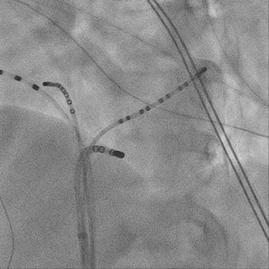

急診室, 3 歲時發作的 12 導程心電圖為 short RP narrow QRS tachycardia ( 圖一、發作時 ) ,因 RP interval 為 120 ms,orthodromic AVRT的可能性較大,retrograde P wave 的型態為I: +/-, II/III/aVF: -, V1: +,delta RP interval of III and V1: 0 ms ,根據 Tai et al. 的研究可以推論可能是 concealed posterior septal accessory pathway(1)。使用 adenosine後,tachycardia可以被矯正回sinus rhythm (圖 二、沒發作時 ) 。自出生後就一直服用 betablocker ,但 仍時常發作,因此在 13 歲時,我們安排了心導管電生 理檢查, RV burst pacing 時最早的 retrograde atrial activation是CS ostium,PAC時會誘發tachycardia (TCL: 446 ms) with the same retrograde atrial activation (concentric) when RV burst pacing (圖三),Ventricular overdrive pacing during tachycardia呈現VAV response with SA-VA of 48 ms and PPI-TCL of 72 ms (圖四),在 VOP 時 fusion beat can reset the next A ( 圖五 ) , Hisrefractory VPC can reset the next A (圖六),在tachycardia 時有出現RBBB pattern也沒有延長TCL (圖七),Antegrade conduction 經由 fast AVN ,綜合以上判斷 orthodromic

AVRT with concealed left posterior septal AP,於是在RV pacing時,我們先從RPS region開始mapping沒有發現有 VA fusion site,然後我們就到retrograde transaortic到LPS region mapping也沒有找到VA fusion的位置,接著我們 的電燒導管在 CS 裡 mapping 時突然掉進 MCV ,這裡發

現有VA fusion (圖八),由於可能很靠近coronary artery

擔心用 RF ablation 會造成 coronary artery stenosis or occlusion(2) ,我們在 ablation 前有先做 coronary angiogram (圖九),coronary artery離VA fusion site都有超 過5 mm,所以我們就使用7F non-irrigated RF catheter在 MCV VA fusion site進行ablation,但是沒有效果,接著 我們做了 CS venogram 發現有一個 CS diverticulum 在 MCV (圖十)(3),我們就把電燒導管移到diverticulum的 neck ( 圖十一 ) ,可以看到 VA fusion ,在 RV pacing 下 50W/50oC 電燒一開始 0.7 秒就 VA block ( 圖十二 ) ,接著 RF booster 120 seconds,post-ablation EP study只有看到 在 V pacing 時有 one fast-slow echo beat , antegrade conduction 有 dual AVNs ,但無法誘發任何 AVNRT or AVRT。病患接受完電燒後,沒有再有心悸的症狀。 (圖一)、發作時12 lead ECG (圖二)、12 lead ECG after adenosine use

)、冠狀動脈攝影

)、冠狀竇攝影發現

)、VA block within 1 second during RF ablation when RV pacing

(圖九 (圖十一)、X光透視成功電燒的位置在diverticulum neck及3D圖上的成功位置 (圖十二 (圖十 CS diverticulum